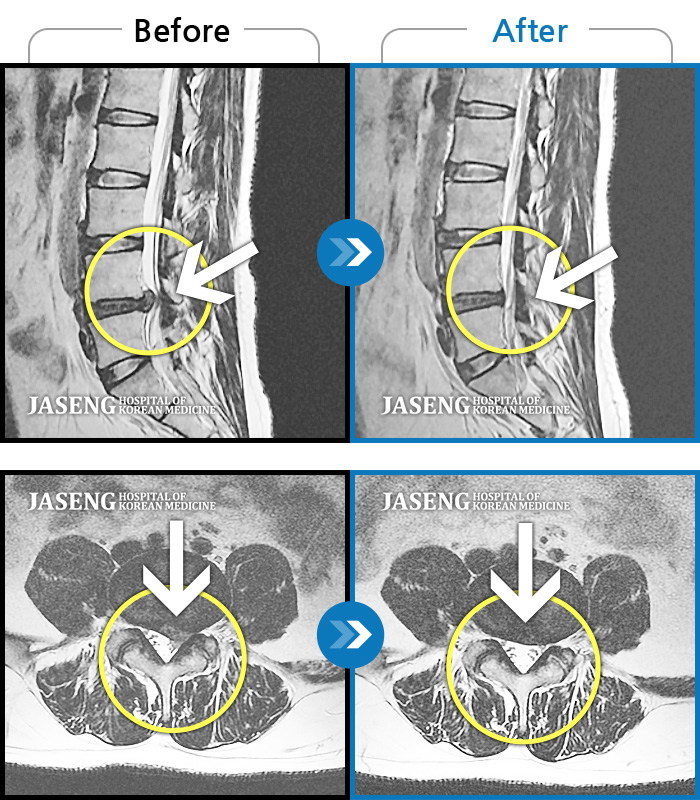

허리디스크

부천 · 신동재 원장

의자 위를 여러 번 올라갔다 내려갔다 반복한 뒤 극심한 하요부 통증 및 좌측 하지부 저림

촬영시기

2024.06.22 ~ 2024.11.19

2024.11.29